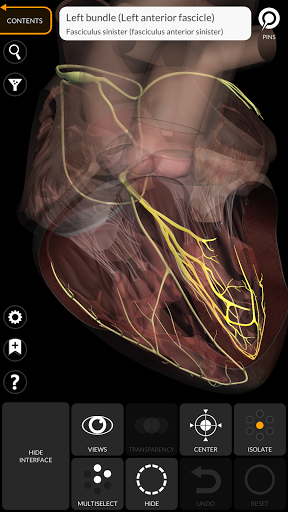

"Anatomía - Atlas 3D" permite estudiar la anatomía humana de forma fácil e interactiva.

A través de una interfaz sencilla e intuitiva es posible observar cada estructura anatómica desde cualquier ángulo.

Los modelos anatómicos 3D son especialmente detallados y con texturas de hasta una resolución de 4k.

La subdivisión por regiones y las vistas predefinidas facilitan la observación y el estudio de partes individuales o grupos de sistemas y las relaciones entre los diferentes órganos.

MODELOS ANATÓMICOS 3D

nervioso • Sistema respiratorio • Sistema digestivo • Sistema urogenital (masculino y femenino) • Sistema endocrino • Sistema linfático • Sistema ocular y auditivo CARACTERÍSTICAS • Interfaz sencilla e intuitiva • Rotar y hacer zoom en cada modelo en el espacio 3D • Opción para ocultar o aislar uno o varios modelos seleccionados • Filtro para ocultar o mostrar cada sistema • Función de búsqueda para encontrar fácilmente cada parte anatómica • Función de marcador para guardar vistas personalizadas • Rotación inteligente que mueve el centro de rotación automáticamente • Función de transparencia • Visualización de músculos a través de niveles de capas desde las superficiales hasta las más profundas • Al seleccionar un modelo o un pin, aparece el término anatómico relacionado • Descripción de los músculos: origen, inserción, inervación y acción • Mostrar/ocultar interfaz de usuario (muy útil con pantallas pequeñas) MULTILINGÜE • Los términos anatómicos y la interfaz de usuario están disponibles en 11 idiomas: latín, inglés, francés, alemán, italiano, portugués, turco, ruso, español, Chino, japonés y coreano • Los términos anatómicos se pueden mostrar en dos idiomas simultáneamente REQUISITOS DEL SISTEMA • Android 8.0 o posterior, dispositivos con al menos 3 GB de RAM Reversi